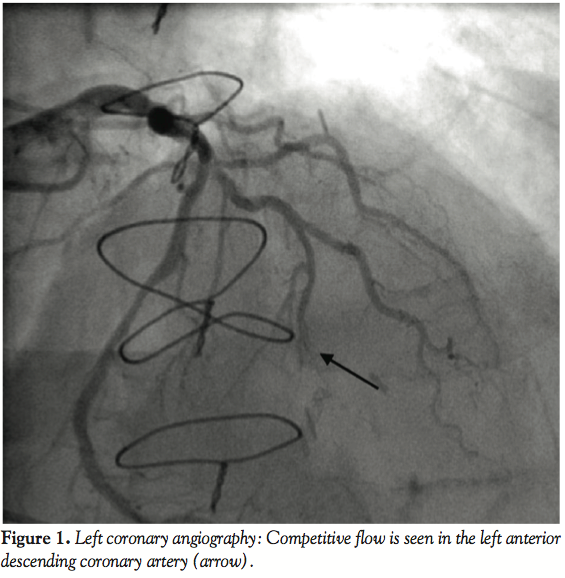

String sign of the left internal mammary artery graft (black arrow …